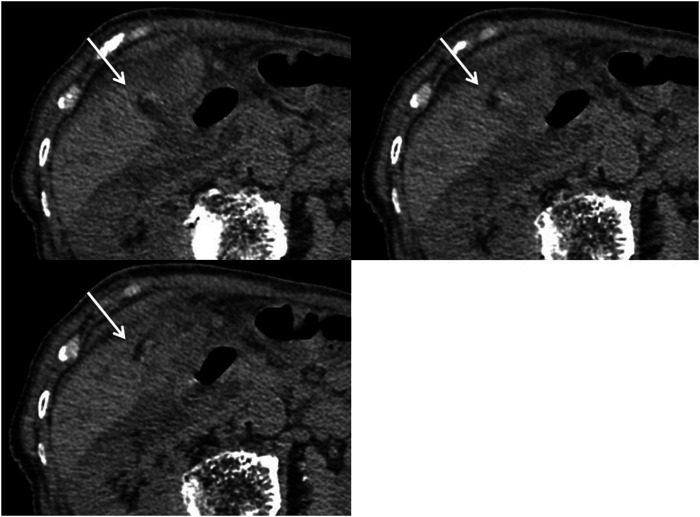

The purpose of this report was to evaluate the usefulness of hyperdense whirl sign on unenhanced computed tomography (CT) for diagnosing gallbladder torsion. The CT scans of seven patients with gallbladder torsion were independently reviewed by two board-certified radiologists for locating the high-density core with twisting between the gallbladder neck and liver bed, termed hyperdense whirl sign. The sign was observed in six cases. The detection of a hyperdense whirl sign on unenhanced CT appears useful for diagnosing gallbladder torsion.

Abstract Image